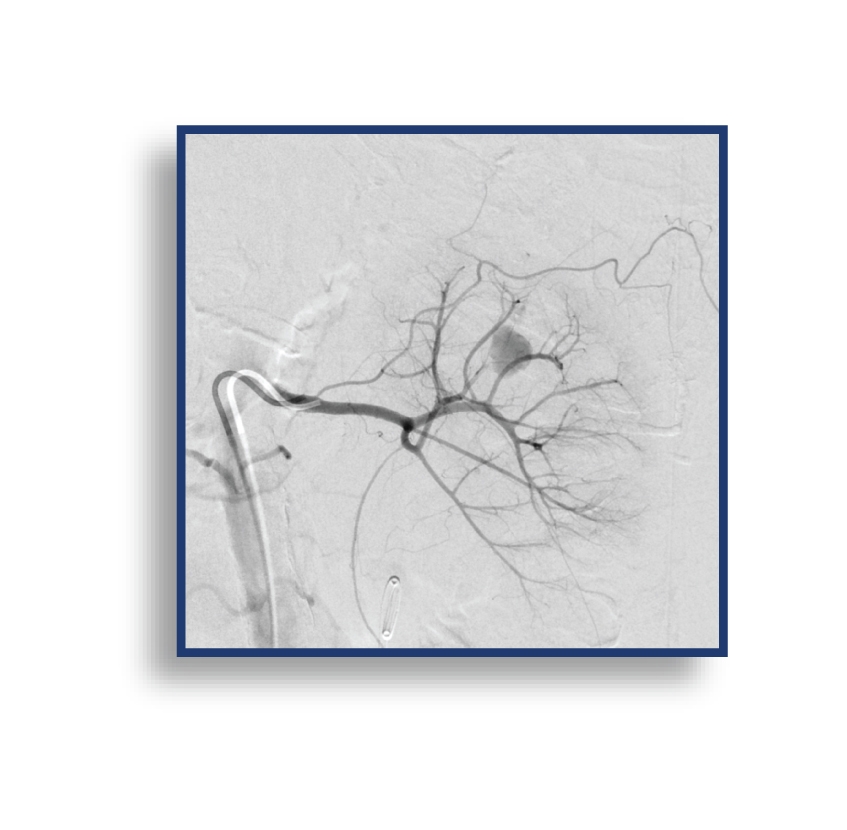

The LAVA Liquid Embolic System (LES) is The First and Only Liquid Embolic Approved for Peripheral Arterial Hemorrhage.

LAVA provides the confidence to quickly stop bleeds results in controlled target vessel occlusion.

LAVA is available in a 2 mL vial and a 6 mL vial; both vials have an 18 or 34 viscosity option. These pre-mixed vials allow for both a proximal target embolization and a distal target embolization, providing options to reach the bleed. The 2 mL LAVA LES comes with two (2) 1 mL delivery syringes and the 6 mL LAVA LES offers six (6) 1 mL delivery syringes, enabling you multi-zone embolization options from 1 pre-mixed vial. An optional Mixing Kit is available to expedite the shaking of the vial, which suspends the radiopaque particles. The volume of the particles in LAVA has been designed to reduce flash for clear imaging.